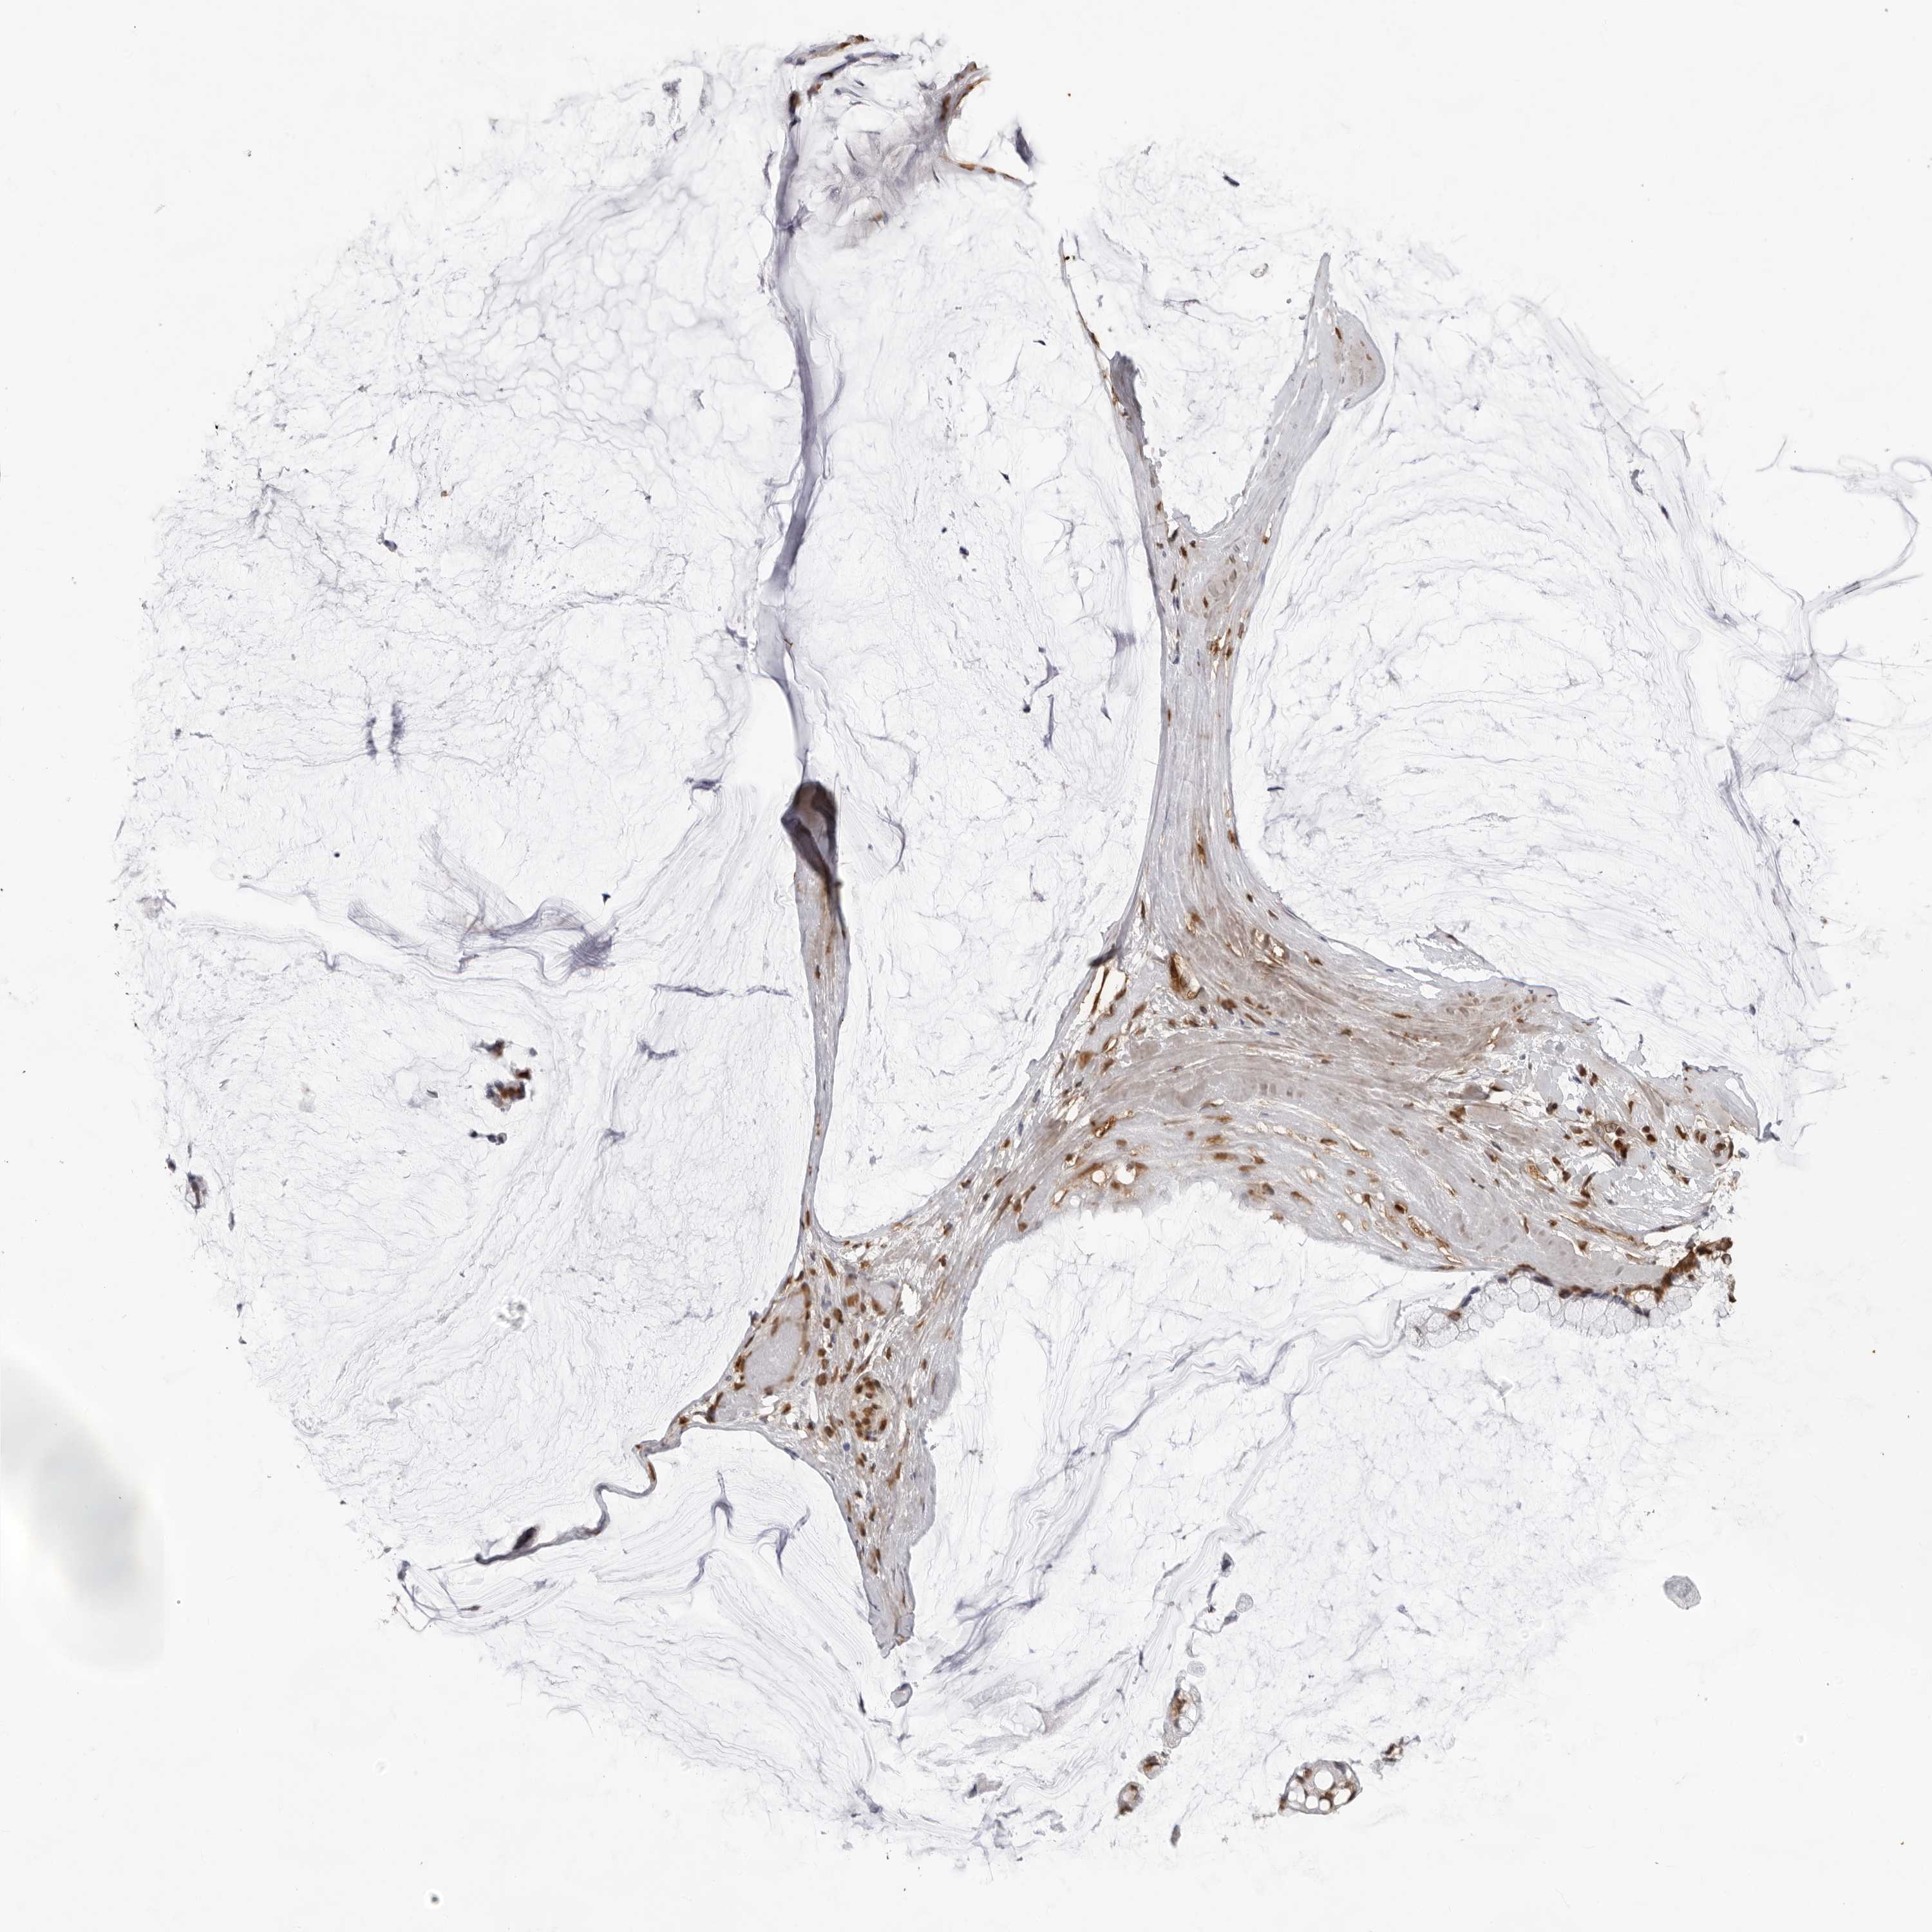

Antibody HPA074591

Staining

High

Medium

Low

Not detected

Intensity

Strong

Moderate

Weak

Negative

Quantity

>75%

75%-25%

<25%

None

Location

Nuclear

Cytoplasmic/membranous

Cytoplasmic/membranous,nuclear

Cystadenocarcinoma, serous, NOS

Carcinoma, endometroid

Cystadenocarcinoma, mucinous, NOS

Carcinoma, NOS